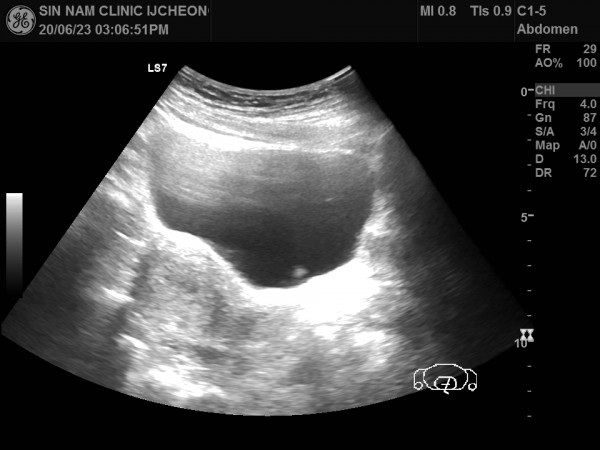

아래 자료는 건강보조식품과 홍삼을 장기 복용한 후 부정출혈이 발생하여 본원에 내원하신 환자분입니다.

내막비후가 지속되어 내막조직검사를 진행하여 내막암 진단을 받으신 분의 초음파 자료입니다.